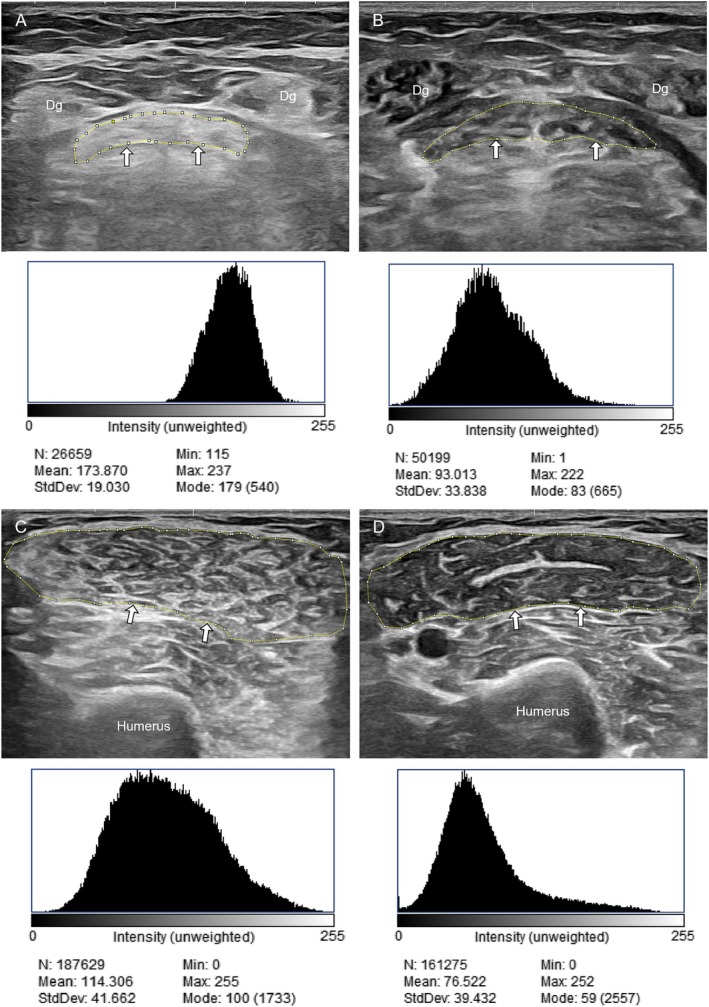

Methods: We analyzed baseline data from an ongoing prospective study involving 23 patients with DMD (aged 5-18 years; mean 10.7; SD 4.2). High-resolution ultrasound scans of muscle groups across the upper and lower limbs, head and neck, and diaphragm were assessed for muscle echogenicity using mean grayscale values (MGV). Functional capacity assessments included the 6-min walk test (6MWT), North Star Ambulatory Assessment (NSAA), Performance of Upper Limb (PUL) module, timed function tests, quantitative muscle strength tests, and respiratory muscle strength tests.

Abstract Image